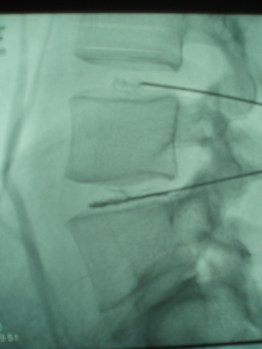

Mientras que la solución tradicional propuesta por muchos neurocirujanos o traumatólogos sigue siendo la cirugía con fijación vertebral (placas, clavos...), el DiscoGel® representa una alternativa eficaz, segura y mínimamente invasiva. Se trata de una sustancia a base de alcohol gelificado (etanol) que, inyectada en el núcleo del disco dañado, reduce la presión interna y desinflama las raíces nerviosas comprometidas.

La intervención se realiza en quirófano con sedación general ligera. Primero se infiltra el DiscoGel en el disco afectado, y posteriormente se administra una pequeña cantidad de corticoide intraarticular para tratar también la articulación facetaria. El procedimiento dura menos de una hora y no requiere anestesia general ni ingreso hospitalario prolongado: el paciente puede caminar por la tarde y regresar a casa al día siguiente.